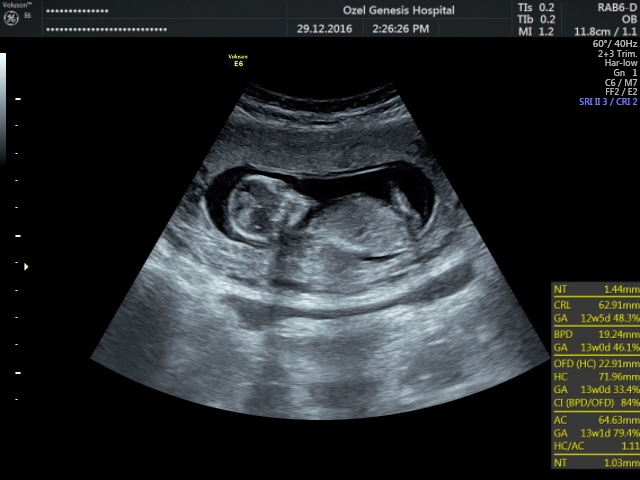

Merhaba , nub teorisine göre cinsiyet tahmini yapan arkadaşımızın dediği gibi resimlerinizin net olması gerekmektedir. Doktorunuz çekim anında görüntüyü net olarak görebilmektedir. Elinize verilen görsel doktorun verdiği görüntü kadar net olmayabilir..Durumu değerlendirilen arkadaşların yolladığı gibi lütfen görselleriniz net olsun.